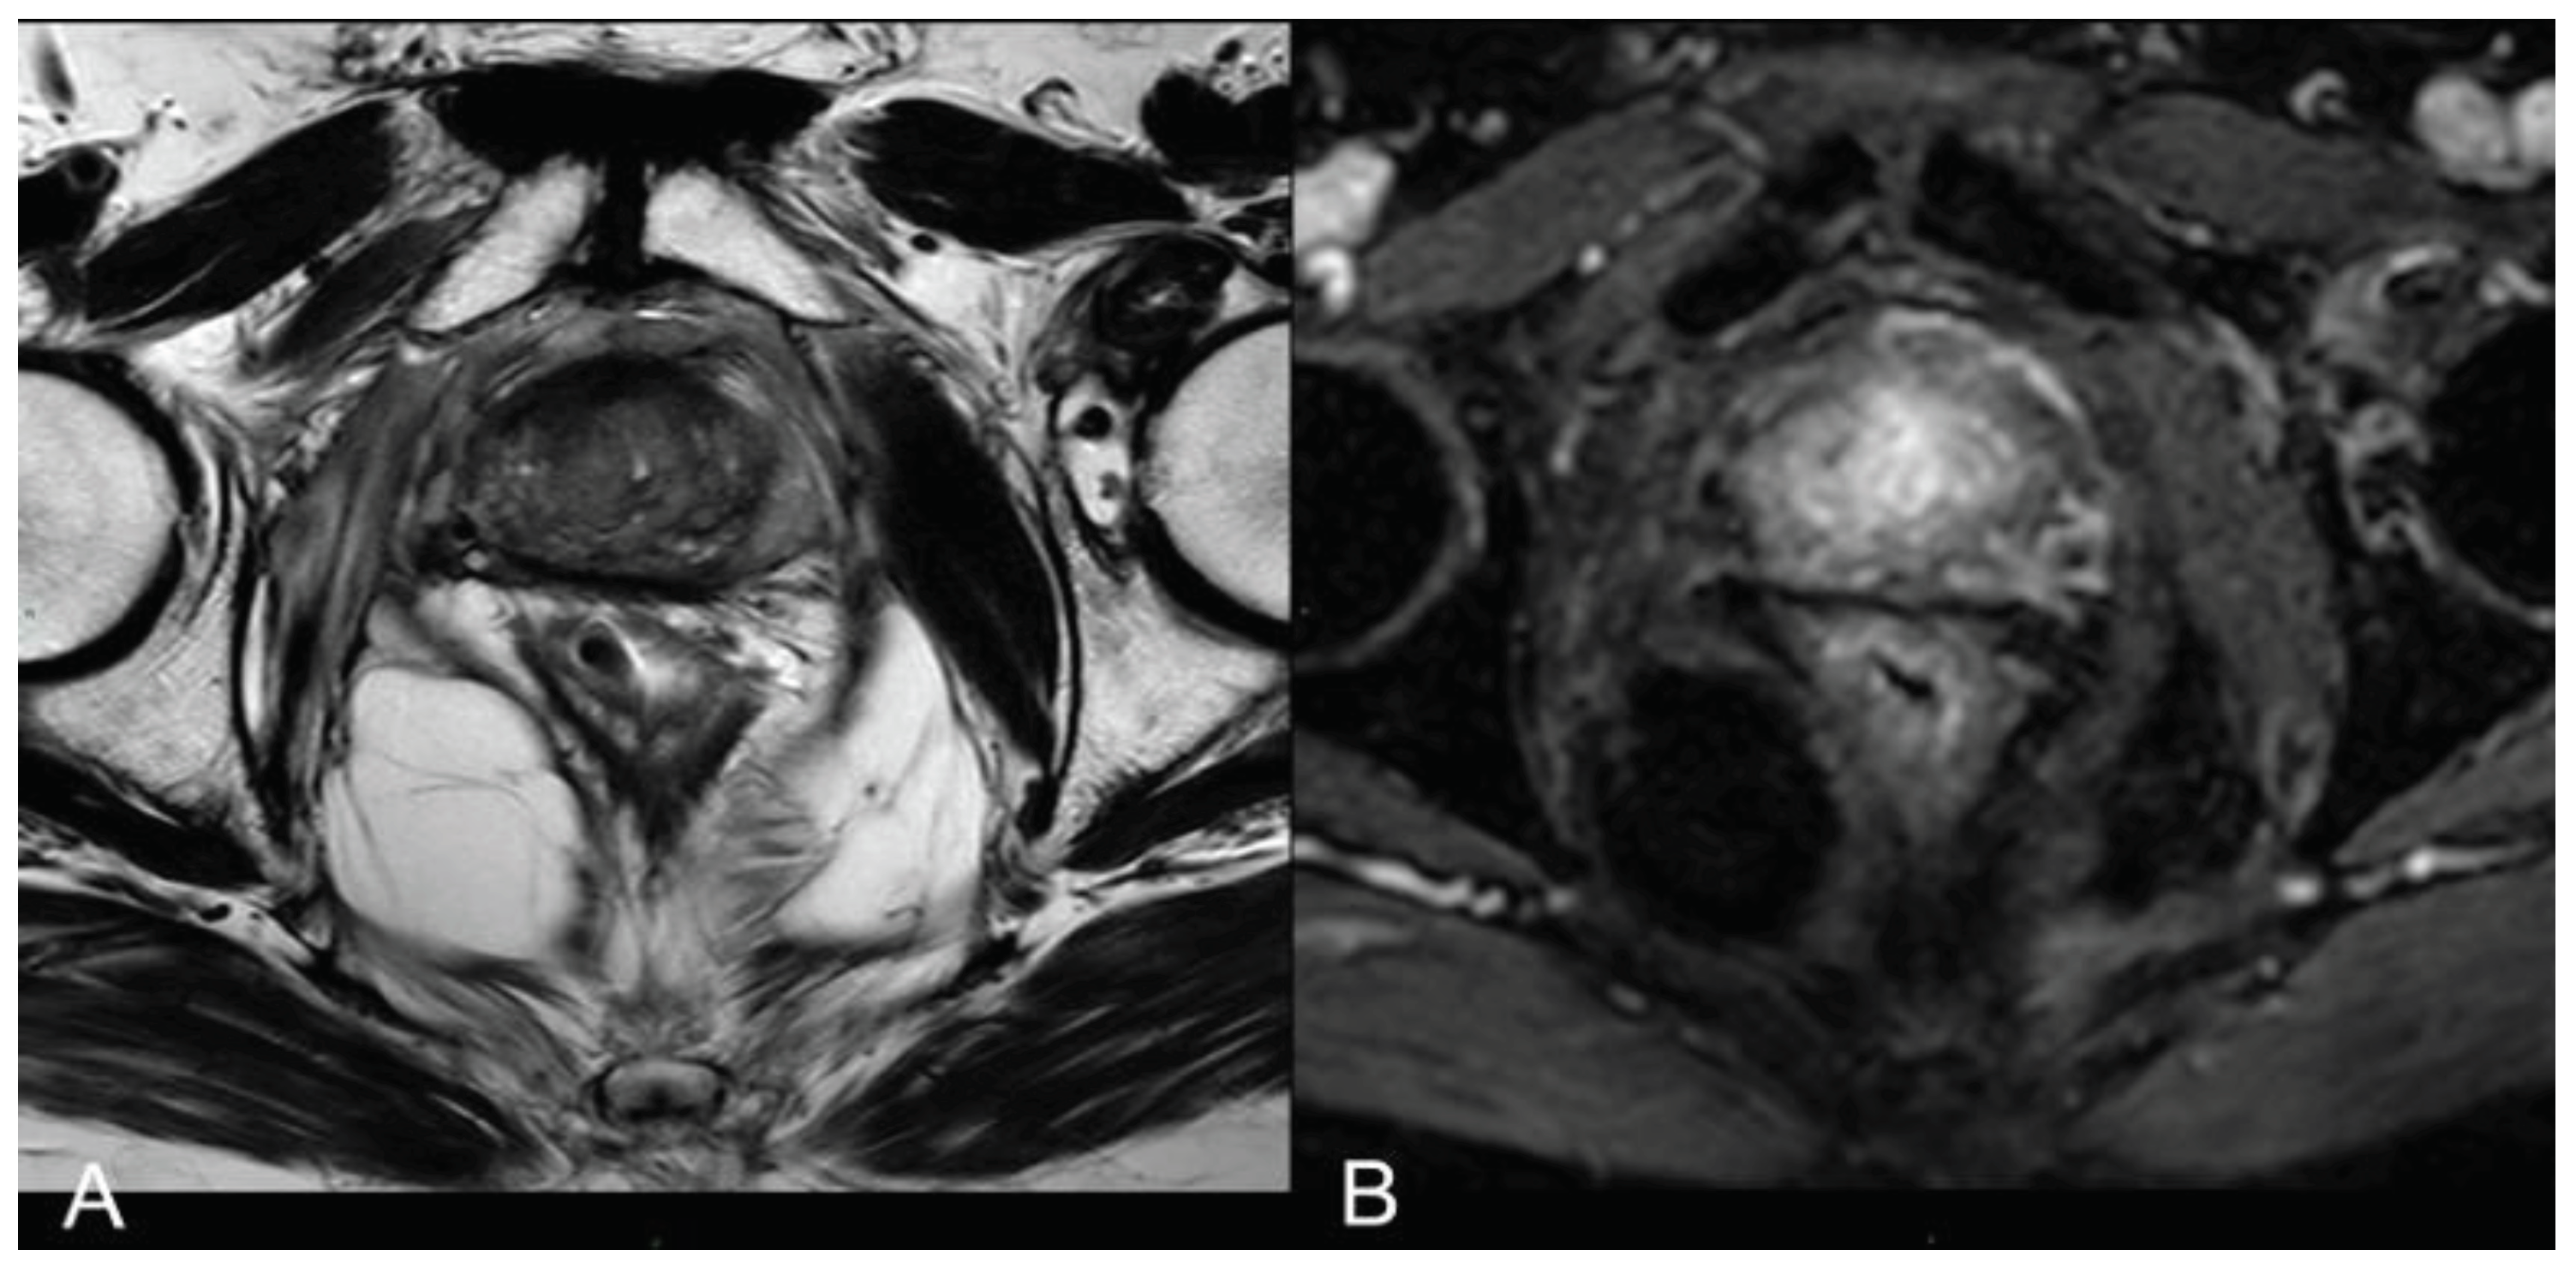

In 25% of the cases, the necrotic coagulation cavity was entirely reabsorbed and replaced by a fibrotic scar, exemplified in Figure 4. Among the 25 patients, 20 did not exhibit any reliable focal contrast enhancement indicative of residual or recurrent neoplastic lesions within the treated area. This absence of neoplasia was subsequently confirmed by MRI/US fusion-guided target biopsies conducted at the 36-month follow-up.

However, for the remaining 5 out of 25 patients, mpMRI at the 12-month follow-up identified a focal lesion adjacent to the ablation cavity in all cases (as depicted in Figure 5), promptly confirmed by target biopsy. In all these instances, the biopsy results indicated Gleason Score 3+4 or 4+3 neoplasm (Table 10). Given the proximity of these lesions to the necrotic cavity, they were all interpreted as indicative of residual cancer.

At 24 months - 36 months: presence of a T2W hypointense scar tissue that almost completely replaced the original cavity (Figure 4).